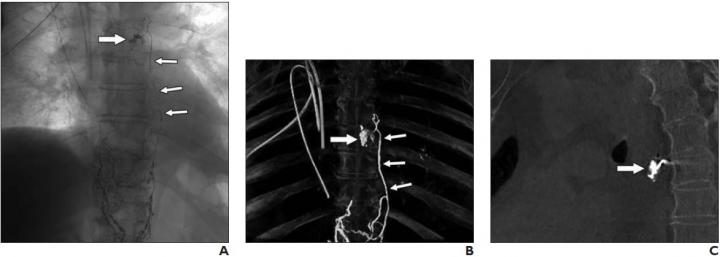

image: Plain thoracic radiograph (A), maximum intensity projection of cone-beam CT image (B), and sagittal cone-beam CT reconstruction (C) show ethiodized oil (Lipiodol Ultra Fluid, Guerbet) extravasation (thick arrow, A-C) projected at left main bronchus 6 days after esophagectomy and thoracic duct ligation were performed. Extravasation is supplied by mediastinal collateral lymph vessels (thin arrows, A and B).